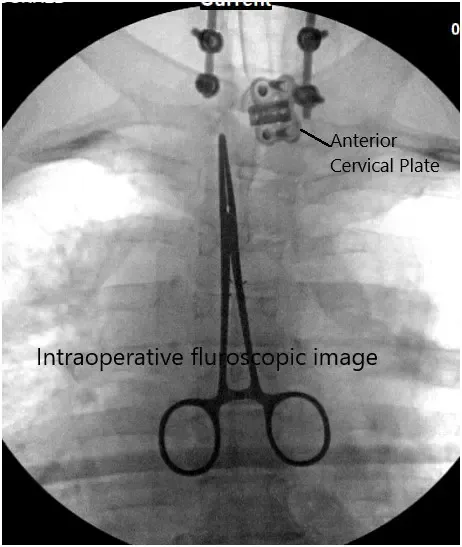

Intraoperative fluoroscopic image.